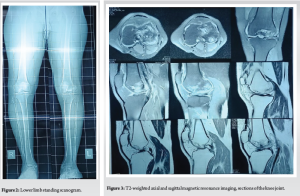

A 17-year-old male with a body mass index of 29.6 presented to our department with complaints of pain over the left knee, difficulty in walking, climbing stairs, squatting, and sitting cross-legged. Detailed history revealed that the patient was diagnosed with ankylosing spondylitis and was prescribed oral steroids for a long duration. He is also diagnosed with clinical depression secondary to the knee disease affliction, and is undergoing pharmacotherapy for the same. He started experiencing pain, locking of the knee in flexion, and difficulty in day-to-day activities, for which he consulted several doctors and was managed conservatively for the same. Despite the ongoing treatments, the patient was not relieved of his symptoms and came to our center for further management. Physical examination revealed lateral joint line tenderness, restricted and painful range of motion with flexion up to 100°. Pre-operative recorded Oxford Knee Score (OKS) was 16, Knee Society Scoring (KSS-K) system of 47, and KSS-F (Functional) of 45. There was no evidence of laxity or instability. On radiological examination, the left knee anteroposterior (AP), lateral, and skyline X-ray (Fig. 1) revealed femoral lateral condyle and trochlea articular surface irregularities with sclerotic changes, subchondral collapse, reduced joint space, and the presence of a loose body in the lateral femoral gutter. Cystic lesions were also noted in the medial femoral condyle with marginal osteophytes. Secondary osteoarthritic changes were noted predominantly in the lateral compartment. The standing X-ray scanogram revealed a valgus alignment of the limb (Fig. 2).

Magnetic resonance imaging (MRI) scan of the knee (Figs. 3, 4, 5) was done which revealed large serpiginous areas of lowsignal intensity on T1W images with double line sign and rim sign on T2W images involving whole of lateral femoral condyle and trochlear surface, subchondral bone collapse and bone marrow edema in lateral femoral condyle, trochlear surface and also part of the medial femoral condyle. Mild joint effusion, along with osteoarthritic changes, was noted.